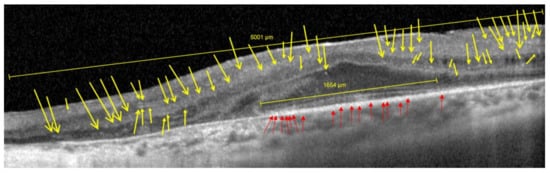

3.1. HRF in RP Patients against Controls (OCT Imaging)

IS-OS Line/Ellipsoid Zone (EZ)